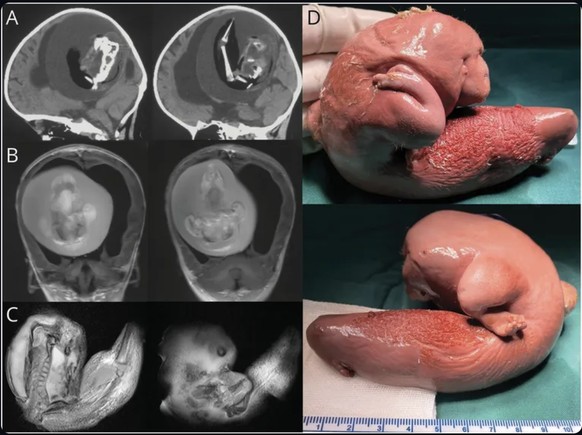

Les photos du fœtus (on vous aura prévenu):

Pendant plus de douze mois, le jumeau parasite est ainsi parvenu à «rester vivant» dans la tête de sa sœur grâce à un apport sanguin constant. Toujours d'après le tabloïd britannique, les médecins ont déclaré que le fœtus qui mesurait 10 centimètres avait développé des membres supérieurs, des os et même des ongles.

Les médecins ont cependant insisté sur le fait qu'il n'aurait pas pu survivre à plus long terme. Dès sa découverte, le jumeau parasite a été retiré chirurgicalement du cerveau de la Chinoise de 1 an avant d'en décéder. Quant à la santé de la fillette, les experts affirment que celle-ci se porte mieux.